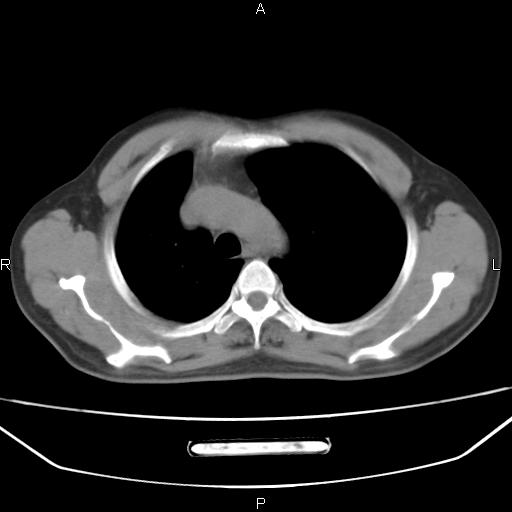

患者,男。50岁。近几日有咳嗽症状,无其他不适,既往病史无,考虑膈疝。请前辈们看看指导指导。

膈膨升,左下肺通气不良,膈肌好像还完整。

考虑左侧膈疝。

左侧膈疝。

符合隔膨升,膈肌较完整。